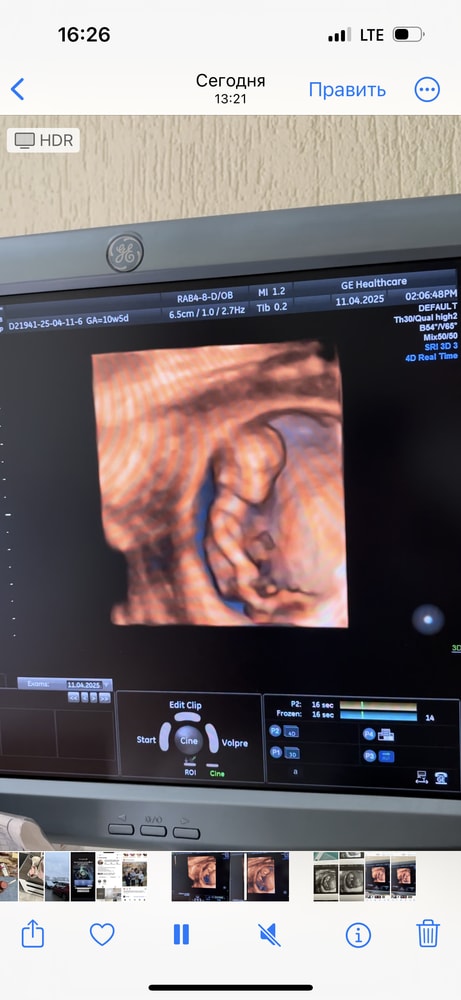

УЗИ 10.5 ❤️ Фото пупсика

УЗИ, КТГ, доплерРешила перед скринингом попасть еще раз на узи, малыш уже совсем человечек) по месячным срок 10.5, по УЗИ 11.1. Очень активный, машет ногами 😂 хотели глянуть пол,но ноги мешали,ну ничего)

Решила перед скринингом попасть еще раз на узи, малыш уже совсем человечек) по месячным срок 10.5, по УЗИ 11.1. Очень активный, машет ногами 😂 хотели глянуть пол,но ноги мешали,ну ничего)